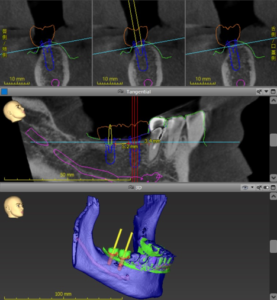

右下の奥歯のインプラント治療を行えるスペースが出来たので、インプラント治療のためのシミュレーションを行いました。

設定したかぶせに対し、良い位置で右下の奥歯2本にインプラントを埋入するようにシミュレーションしました。